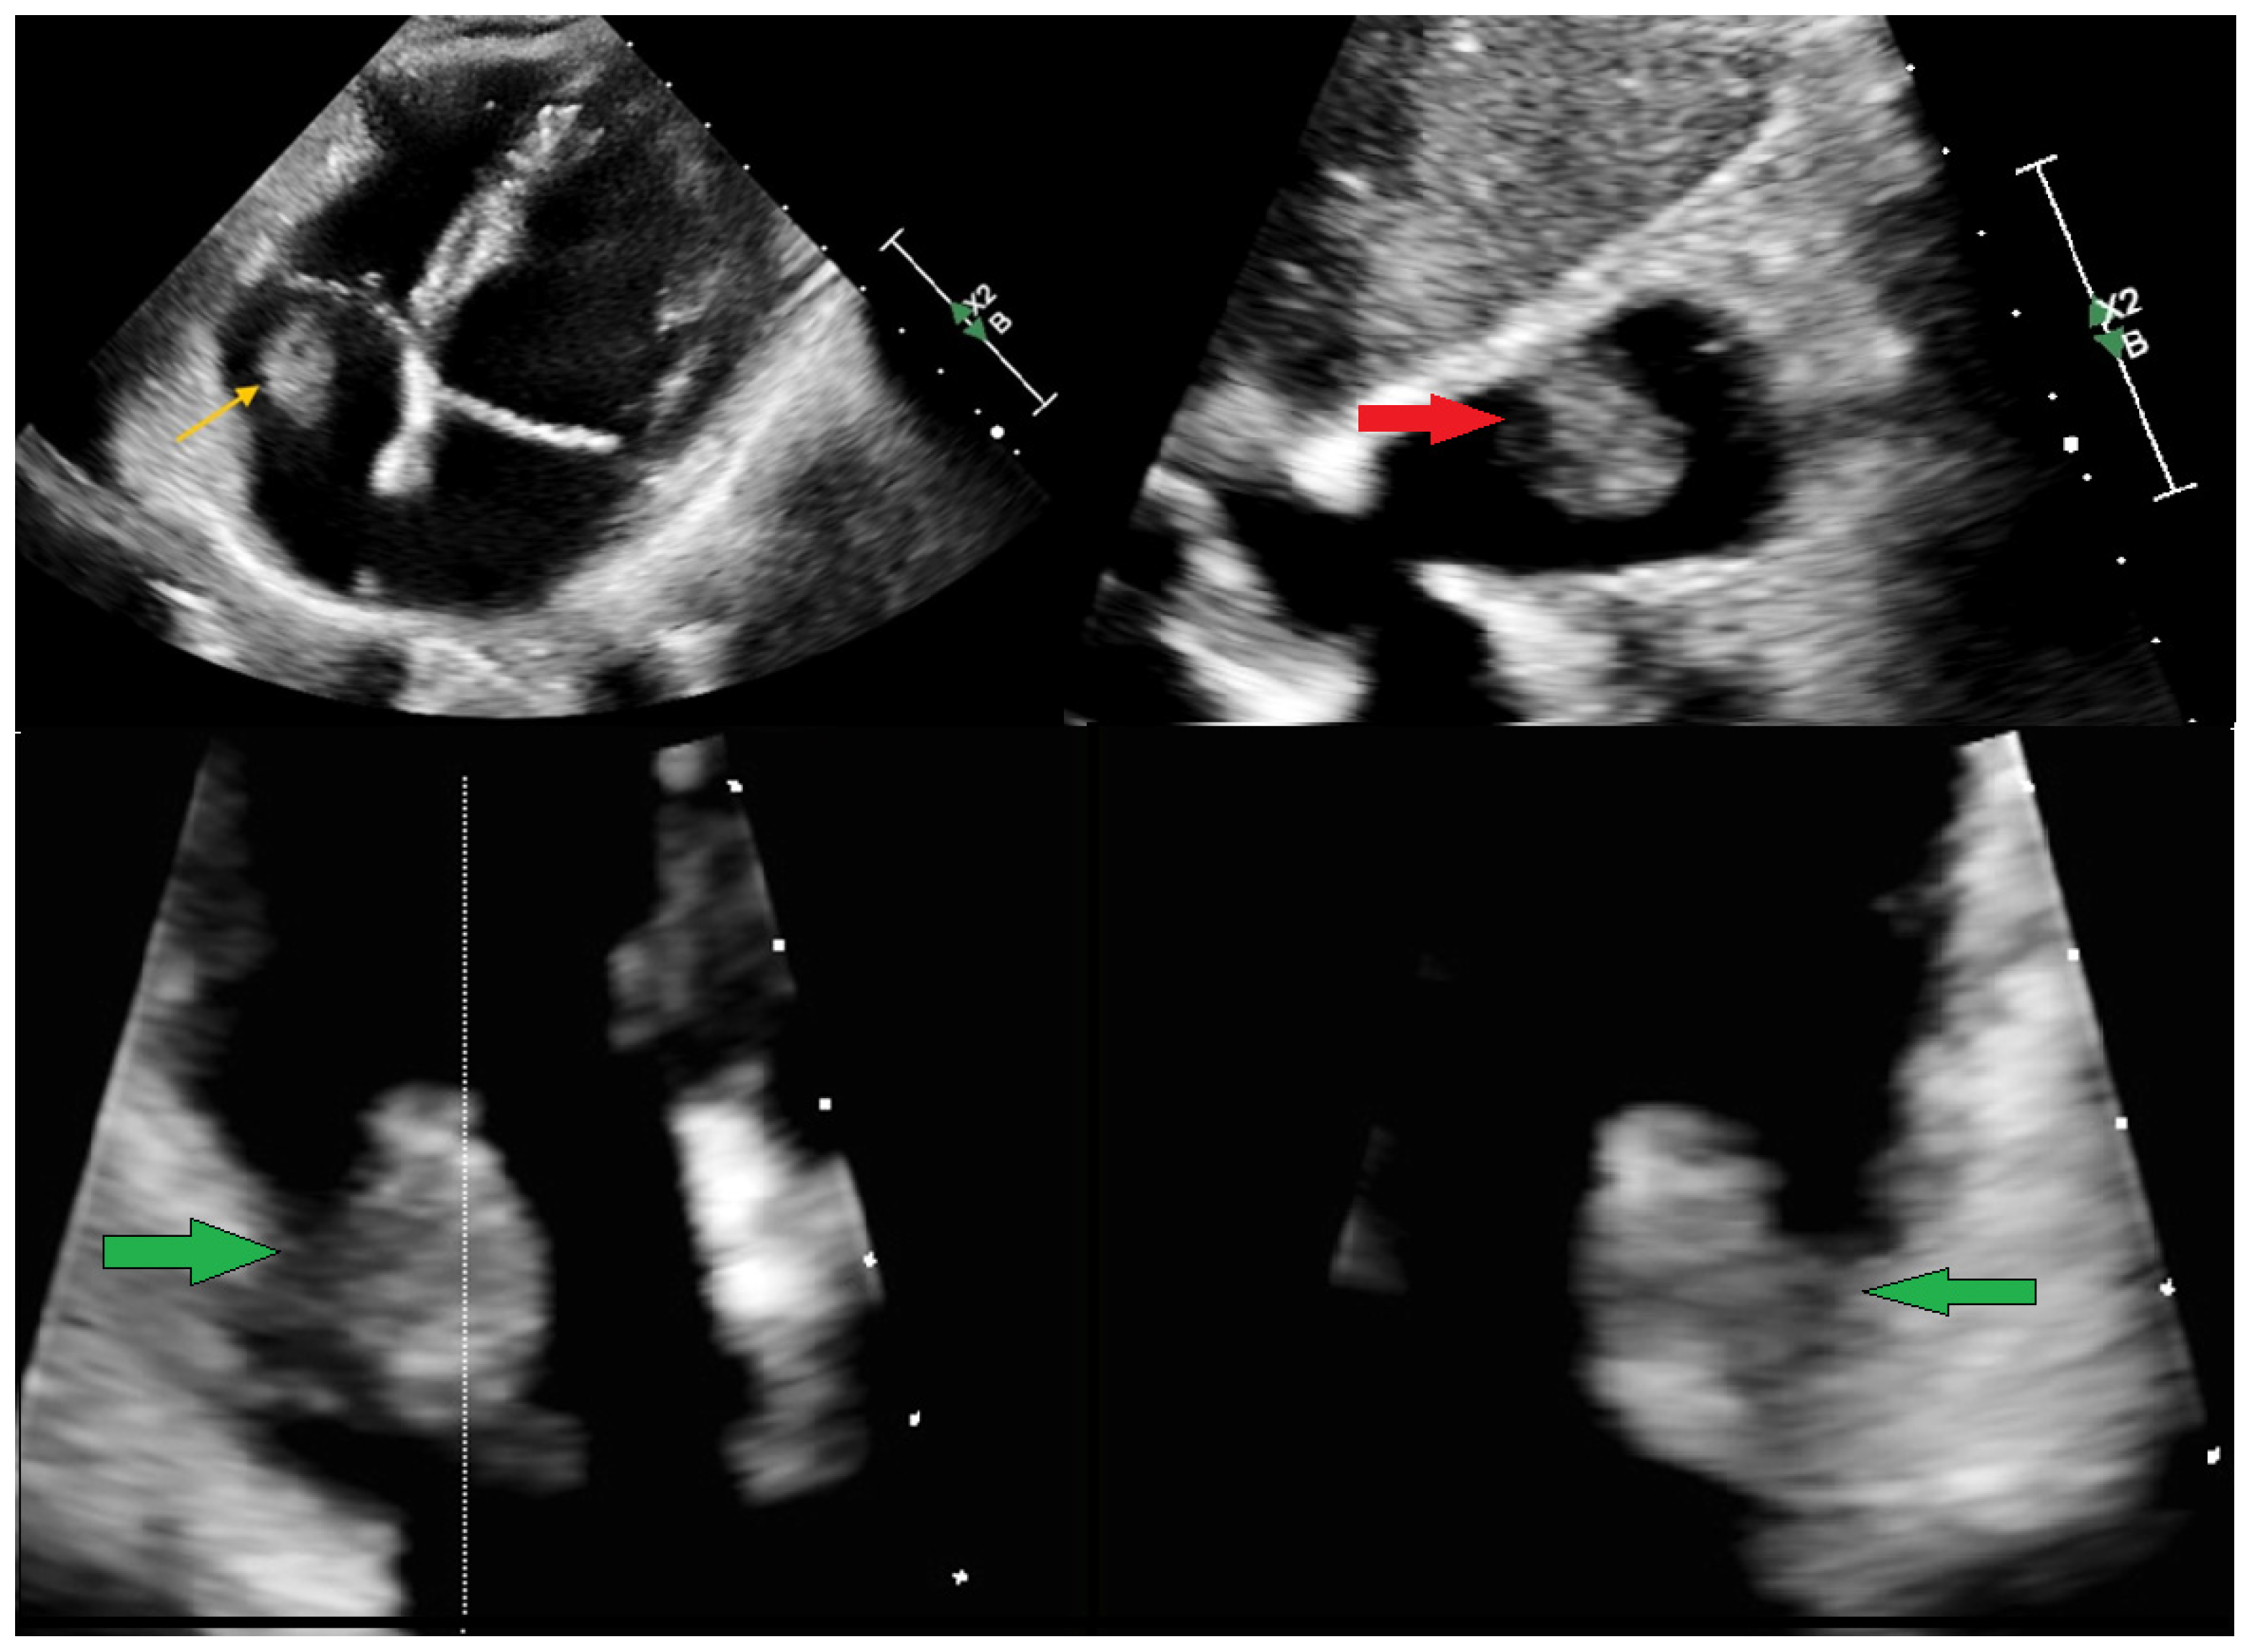

A Multi-Modality Approach to the Assessment of a Right Atrium Mass in a Female Patient with Breast Cancer Undergoing Neoadjuvant Chemotherapy

Chlabicz, M.; Muszyński, P.; Kruszyńska, J.; Kazberuk, P.; Róg-Makal, M.; Lipowicz, M.; Matys, U.; Tomaszuk-Kazberuk, A.; Kożuch, M.; Dobrzycki, S. A Multi-Modality Approach to the Assessment of a Right Atrium Mass in a Female Patient with Breast Cancer Undergoing Neoadjuvant Chemotherapy. Diagnostics 2025, 15, 2683. https://doi.org/10.3390/diagnostics15212683